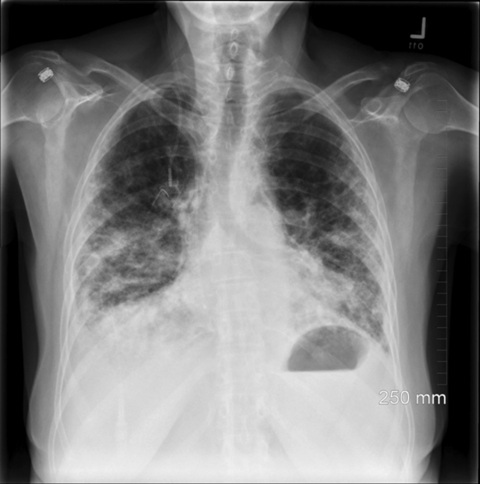

Thursday 3rd July 5.1 Normal question prior to Chemo but I tell the doctor that over the past week I felt a little breathless. So I’m sent off for a respiratory test. I had this test prior to ABVD in March and the results back then showed 90% volume intake which was excellent, but this one showed 47% which was bad. So off to X-Ray department for a chest X Ray and back to the ward.

Basically the B – Bleomycin can cause your lungs to collapse, it’s not a normal side effect as it only effects 1 out of 50 but yes I just happen to be the 1.. My oncologist explained that to continue using Bleomycin would basically destroy my lungs, my right lung was seriously damaged and further exposure could kill me. So they stopped the Bleomycin. From 5.1 onwards I’m on AVD.